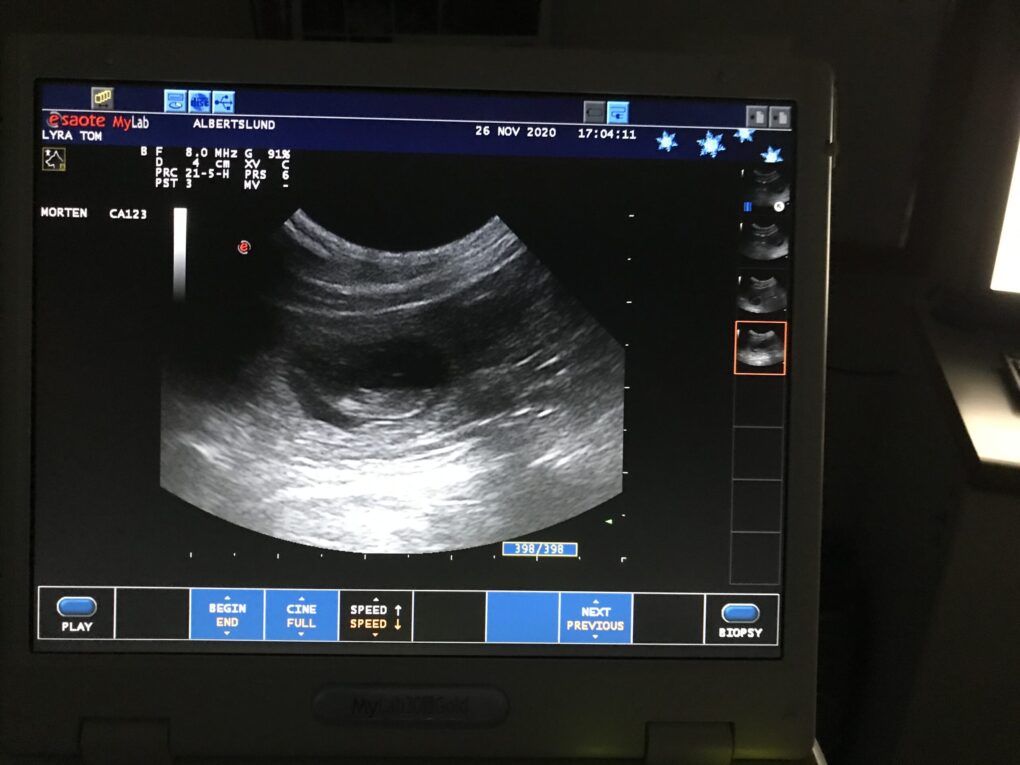

I sidste uge var vi en tur forbi dyrlægen. Scanningen viste, at parringen havde været vellykket – jubii!